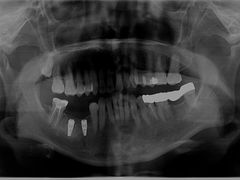

• 爱贝口腔·牙周诊疗·种植修复中心

• -爱贝口腔·牙周诊疗·种植修复中心

匿名用户 | 23-10-27